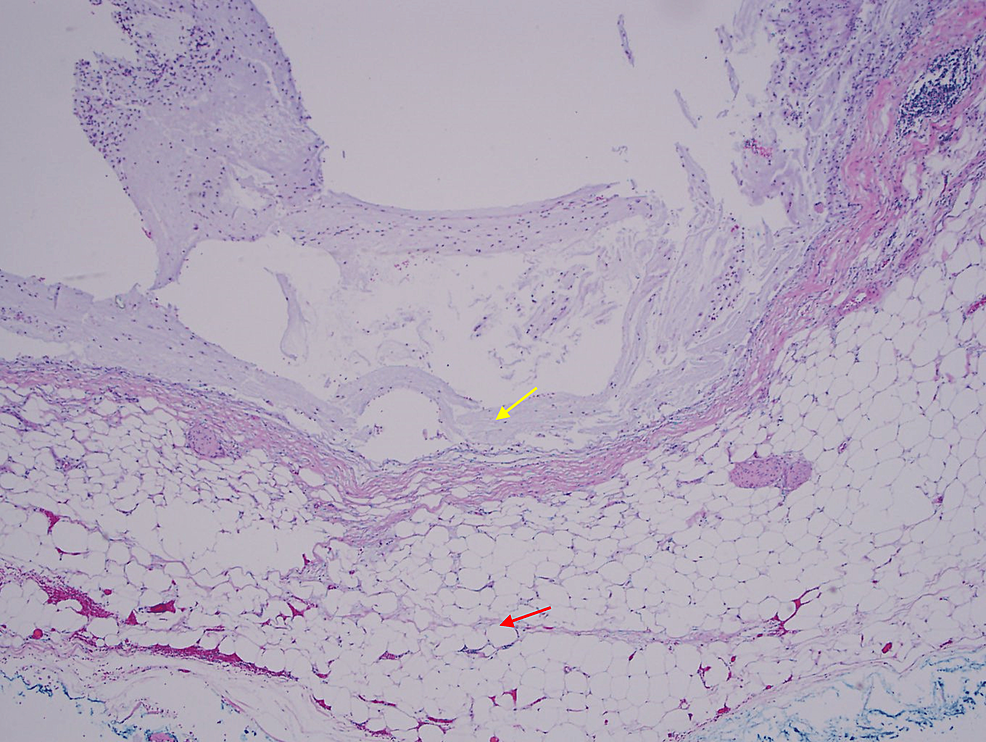

To evaluate for the development of PMP and metastasis and assess whether LAMN is present, a pathological examination is needed for further analysis. While frozen sections are sometimes obtained for diagnosis and resection margin analysis, they may not be helpful for diagnosis given the complexity of LAMN pathology and the limited correlation of frozen sections with the final pathology [9]. Pathologically, LAMN is characterized by atypical glandular cells, neoplastic mucinous epithelium, back-to-back crypts, sparse lamina propria, and extended villi (Figure 6) [1-2]. It grows outward via “pushing” invasion, creating dissected or tongue-like epithelium and diverticula [2]. Mucin and neoplastic epithelium may dissect through the muscularis propria and even breach the appendiceal wall, seeding into the peritoneum and progressing to PMP (Figure 7) [2]. However, there are no signs of “infiltrative” invasion such as budding, single-cell invasion, or desmoplastic stromal reaction [2].

Staging is vital to examine for dissemination of mucin and neoplastic cells into the peritoneum and progression to PMP and metastasis. In pTis(LAMN), the LAMN is confined to the appendiceal wall, although acellular mucin or mucinous epithelial cells may still extend into the muscularis propria but not the mesoappendix or serosa [10]. In pT3, LAMN with acellular mucin or mucinous epithelium invades into the subserosa or mesoappendix but not the serosa [10]. In pT4, LAMN with acellular mucin or mucinous epithelium invades into the serosa of the appendix or mesoappendix (pT4a) or directly invades adjacent organs and structures (pT4b) [10]. In M1a, acellular mucin is disseminated intraperitoneally [10]. In M1b, metastasis occurs in the peritoneum [10]. In M1c, metastasis extends beyond the peritoneum [10]. If peritoneal metastasis or PMP is detected, the patient may require cytoreductive surgery (CRS), heated intraperitoneal chemotherapy (HIPEC), or early post-operative intraperitoneal chemotherapy (EPIC) [2,11]. CRS includes peritonectomy and clears away tumor cells to enhance the penetrability of HIPEC and EPIC [2,11]. After CRS and HIPEC, EPIC can be used to augment intraperitoneal therapy against tumor deposits [11].